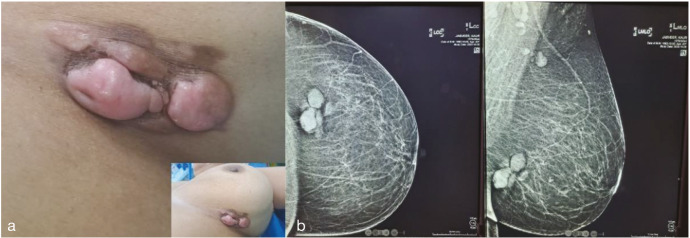

摘要隆突性皮肤纤维肉瘤(DFSP)是一种罕见、低级别、源自真皮层的纤维母细胞间充质肿瘤。乳房是一个罕见的部位,发病率仅为0.8-4.5%,在任何部位的总体发病率为4.2-4.5 /百万人。手术切除2-3厘米的边缘是金标准治疗。选定的病例接受放疗或伊马替尼全身治疗。由于罕见的表现,我们报告一例类似的左乳DFSP病例,患者为42岁女性,她最初被诊断为左乳良性叶状瘤,最终的组织病理学报告显示广泛的局部切除标本诊断为乳腺DFSP。

Dermatofibrosarcoma protuberans (DFSP) is a rare, low-grade, fibroblastic mesenchymal tumor derived from the dermis. Breast is an uncommon site with an incidence of only 0.8-4.5% and an overall population incidence at any site of 4.2-4.5 per million. Surgical excision with 2-3 cm margin is the gold standard treatment. Selected cases are subjected to radiotherapy or systemic therapy with Imatinib. Due to the rare presentation, we report a similar case of DFSP on the left breast in a 42-year-old woman, who was initially diagnosed with benign phyllodes tumor of the left breast and final histopathology report of the wide local excision specimen diagnosed DFSP of the breast.